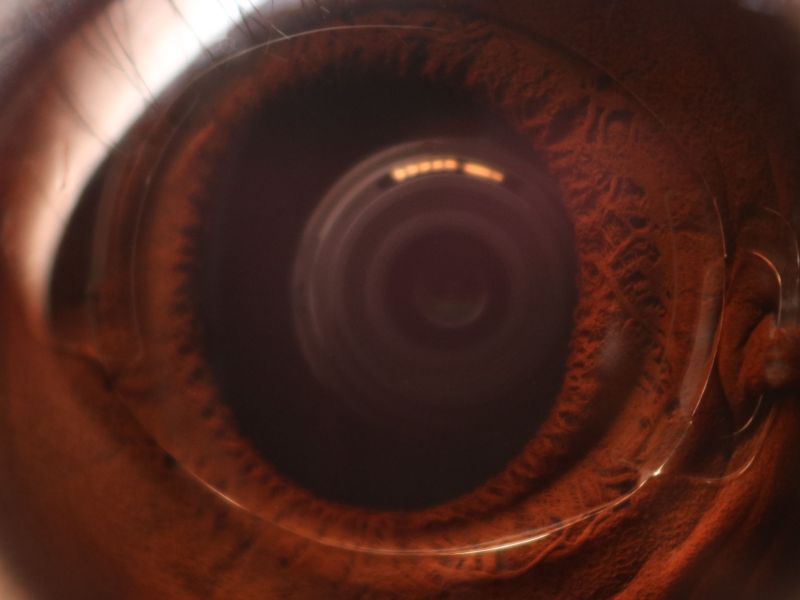

Déficit visual severo en pediatría

Un artículo publicado en el último número de la revista Paediatrics and Child Health, presenta una revisión acerca del déficit visual severo, una condición que trae consecuencias graves para la salud, el desarrollo y la calidad de vida de los niños afectados por esta enfermedad. Entre los aspectos que vale la pena destacar en esta revisión, se incluyen: